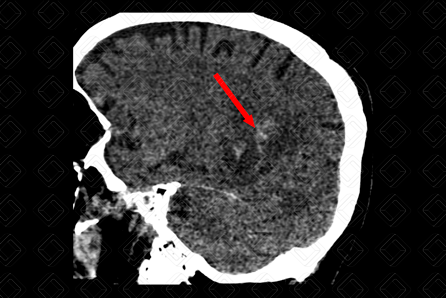

Texto alternativo para a imagem Figura 2. Créditos: Dra. Elazir Mota - Rio de Janeiro/RJ

Descrição das figuras 1 e 2: Tomografia computadorizada do crânio, estudo sem contraste (paciente com injúria renal aguda), planos axial e sagital, evidenciando lesão infiltrativa, de limites mal definidos, heterogênea, com áreas de sangramento, na substância branca profunda do lobo parietal direito (setas vermelhas). O histopatológico revelou que trata-se de glioblastoma.

• Tomografia computadorizada do crânio com contraste venoso: Tumor mais frequentemente na região supratentorial, com preferência pelos lobos frontal e parietal, infiltrando a substância branca. Trata-se de lesão expansiva, em geral, volumosa no momento do diagnóstico, hipodensa ou isodensa, de limites mal definidos e necrose central. Em 95% dos casos, apresentam ávida captação pelo contraste venoso (realce pode ser heterogêneo, irregular ou anelar) (f iguras acima);